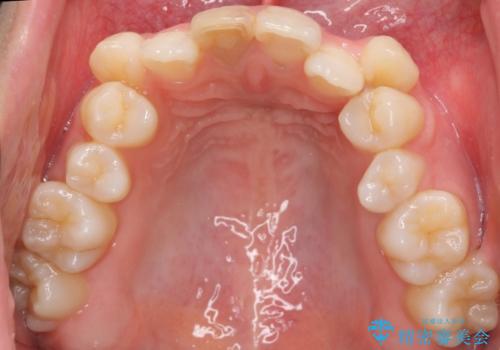

八重歯 前歯のがたがた 抜歯してワイヤー矯正

- 前歯のがたがたを主訴に来院。

八重歯と、前歯のやや開咬の症状もあり難易度としては中等度でした。

上下左右の小臼歯を抜歯し、ワイヤー矯正を行いました。

犬歯のコントロールが難しく、矯正用ミニスクリューを併用しました。

奥歯の歯の間が狭く、ミニスクリューを入れるのも難しい症例でした。

右上の前歯は変色もあり、神経の治療後にセラミックを被せる予定です。